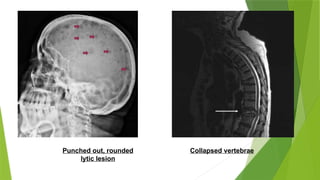

๏ต Hypercalcemia due to increased osteoclastic activity and decreased

osteoblastic activity

๏ต Lytic lesions(0.5cm bone destruction)

๏ต Bone pain is the most common symptom,mainly involves the axial

skeleton and induced by movement

๏ต No osteoblastic new bone formation,hence bone scan is less useful

than plain x ray.

Punched out, rounded

lytic lesion

Collapsed vertebrae